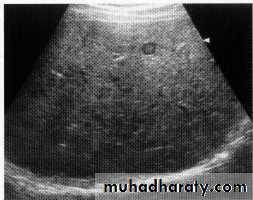

Normal liver U/S

Hepatic mets.